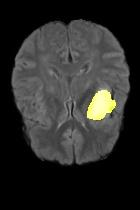

Current unsupervised anomaly localization approaches rely on generative models to learn the distribution of normal images, which is later used to identify potential anomalous regions derived from errors on the reconstructed images. However, a main limitation of nearly all prior literature is the need of employing anomalous images to set a class-specific threshold to locate the anomalies. This limits their usability in realistic scenarios, where only normal data is typically accessible. Despite this major drawback, only a handful of works have addressed this limitation, by integrating supervision on attention maps during training. In this work, we propose a novel formulation that does not require accessing images with abnormalities to define the threshold. Furthermore, and in contrast to very recent work, the proposed constraint is formulated in a more principled manner, leveraging well-known knowledge in constrained optimization. In particular, the equality constraint on the attention maps in prior work is replaced by an inequality constraint, which allows more flexibility. In addition, to address the limitations of penalty-based functions we employ an extension of the popular log-barrier methods to handle the constraint. Comprehensive experiments on the popular BRATS'19 dataset demonstrate that the proposed approach substantially outperforms relevant literature, establishing new state-of-the-art results for unsupervised lesion segmentation.